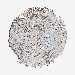

BRCA TCGA BRCA VALIDATION PROTEIN EXPRESSION